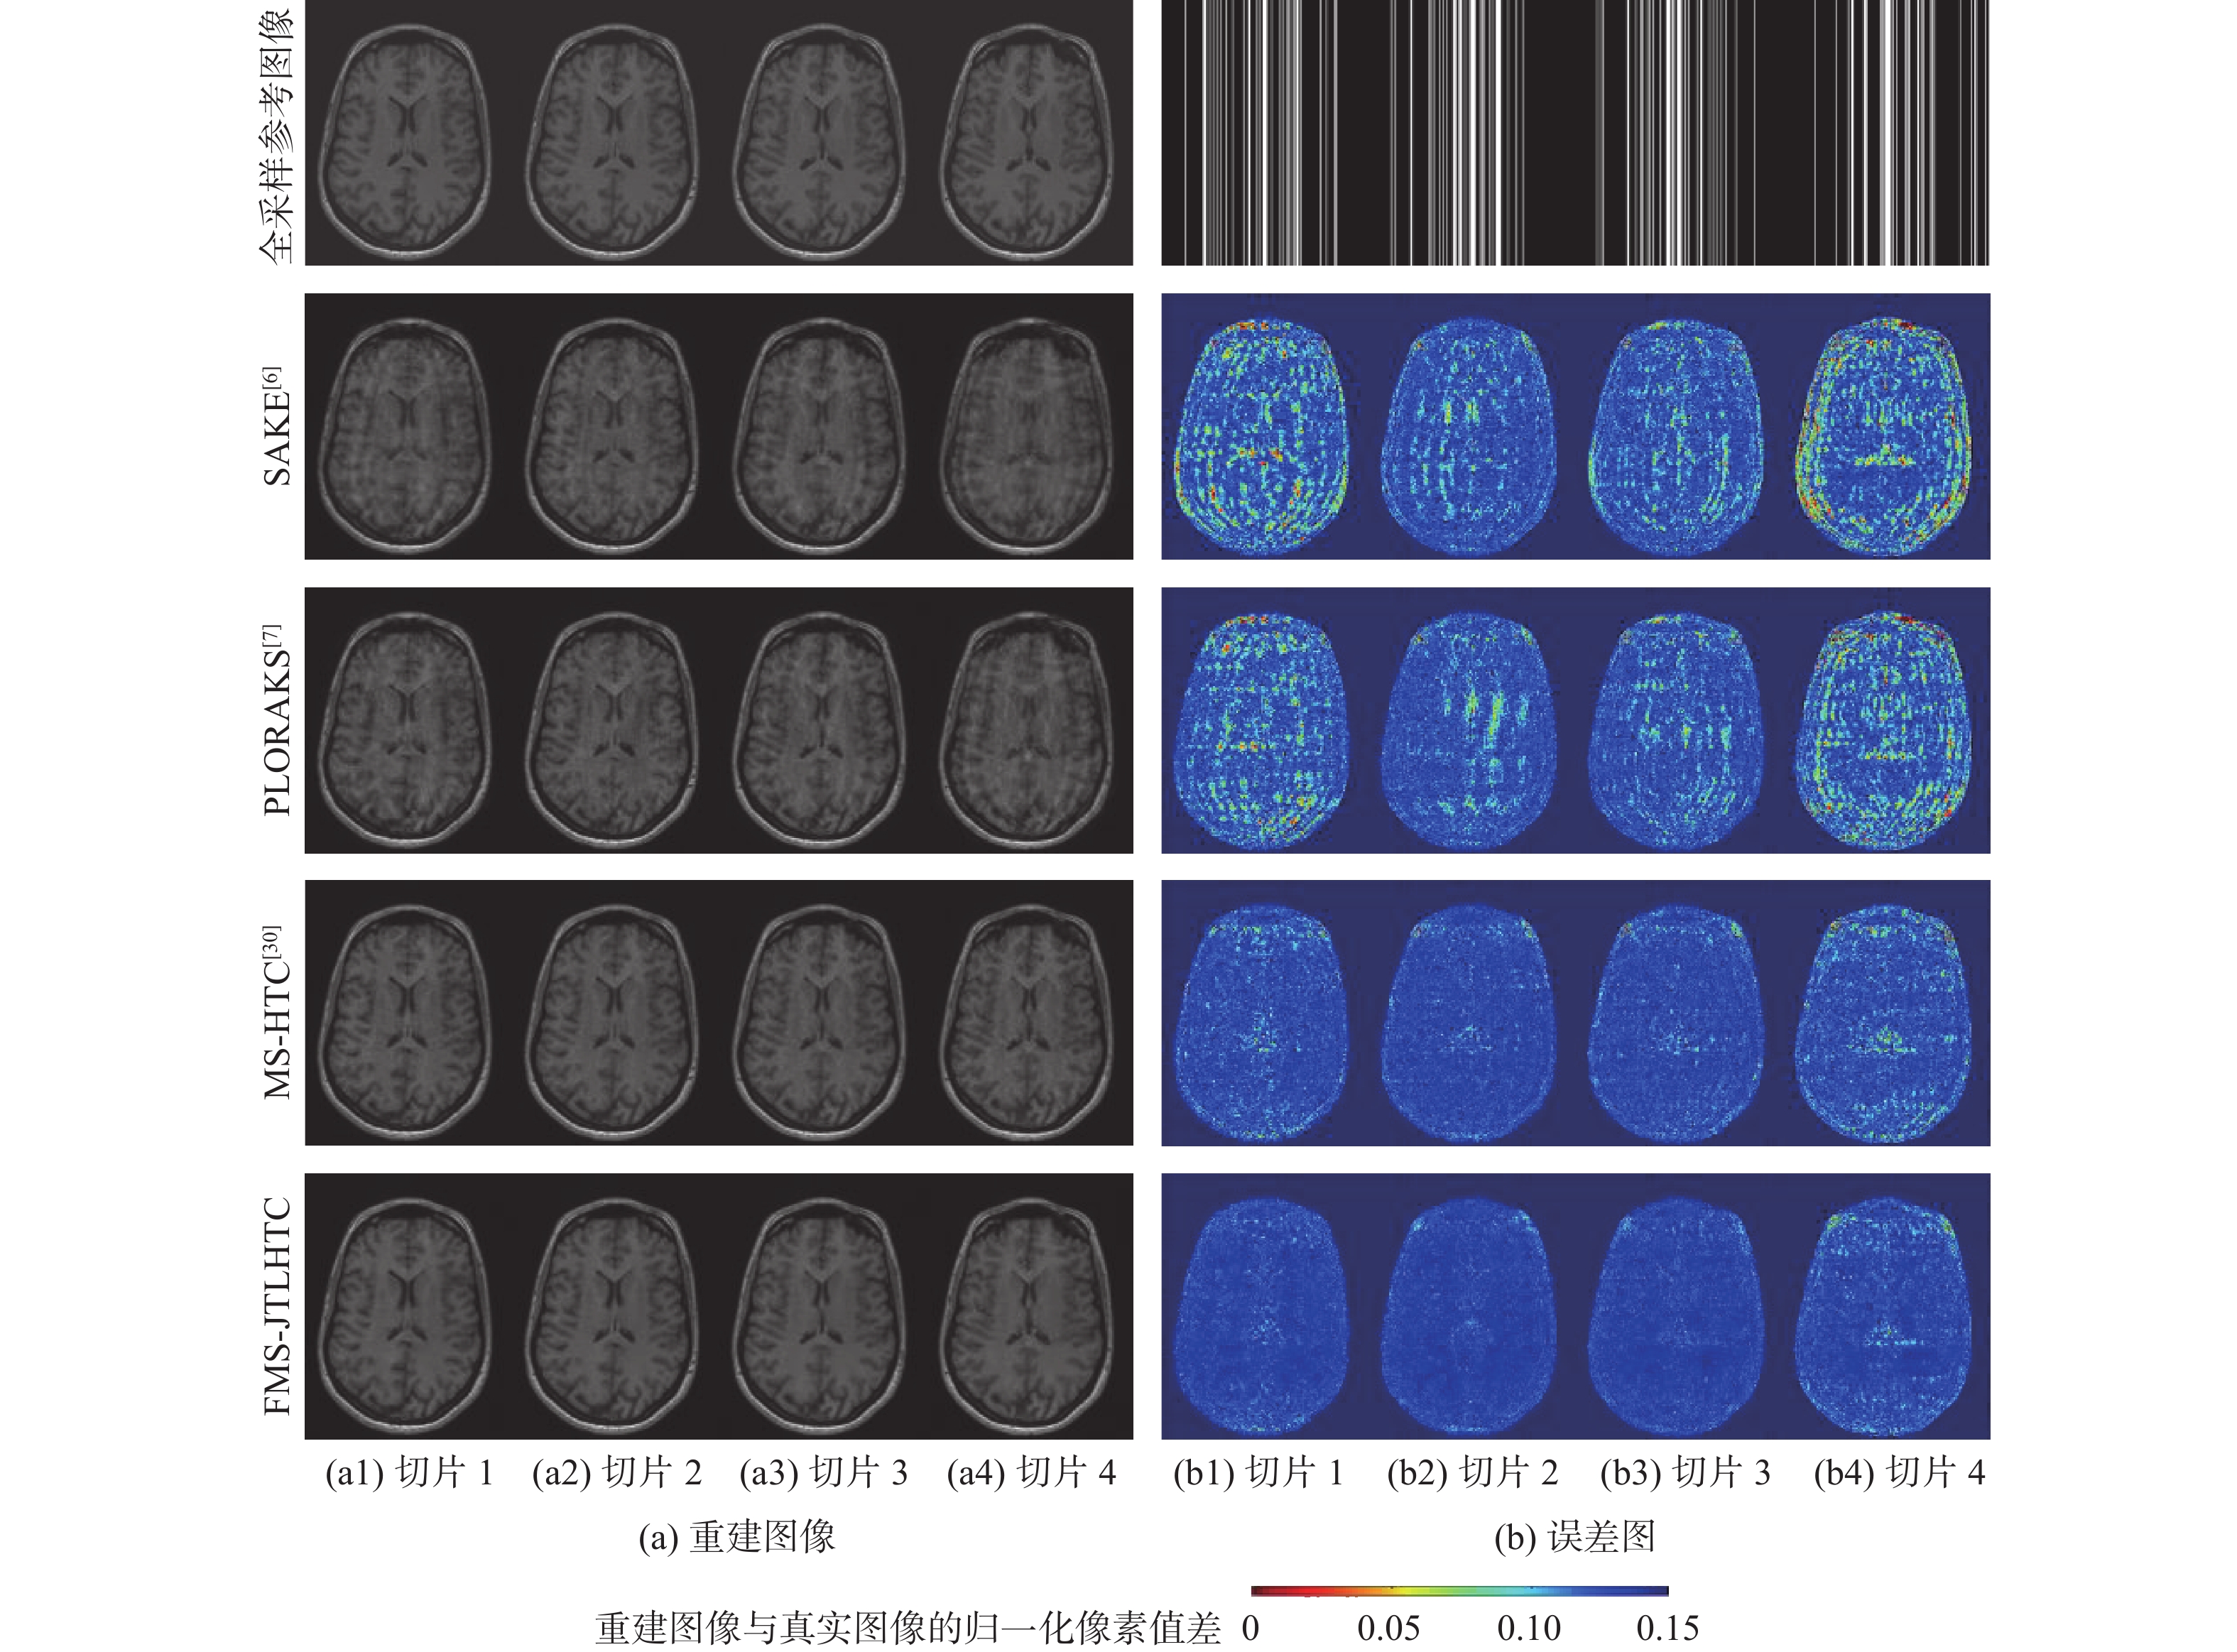

A low-dose CT deep unfolding network based on a sparse transform priors constrain

WANG Yue, ZHANG Xiong, SHANGGUAN Hong, CUI Xueying, ZHANG Pengcheng, GUI Zhiguo

2026, 52(4): 1199-1210. doi: 10.13700/j.bh.1001-5965.2024.0049

Abstract:

Deep iterative unfolding networks have garnered a lot of attention lately because of their great learning capabilities and good interpretability. The regularization terms in existing CT image reconstruction methods mostly focus on information within a specific domain, leading to issues such as edge blurring and information loss in the reconstructed results. Therefore, a sparse transform prior constrain based deep unfolding network is proposed for sparse-view CT reconstruction. Two regularization terms with complementary information—transform-domain sparse regularization and pixel-domain consistency regularization—are created in consideration of the important roles that both pixel-domain and transform-domain information play in picture reconstruction. Based on these, the objective function for sparse-view CT reconstruction is redesigned. Furthermore, a new deep unfolding network for iterative reconstruction of low-dose CT is created by mapping a set of constraint relationships established from an iterative optimization solution for the constructed objective function. Experimental results demonstrate that the algorithm presented in this paper achieves a great improvement on average peak signal to noise ratio (PSNR) and visual information fidelity (VIF) compared to the classical FISTA algorithms.